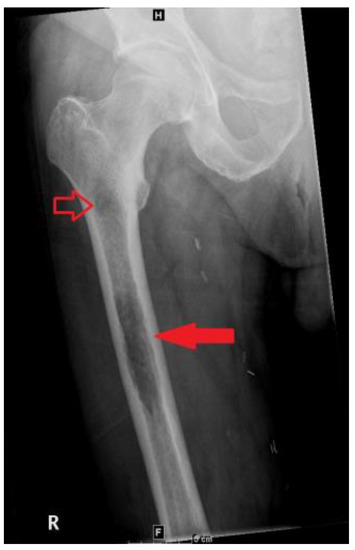

2. Case Presentation